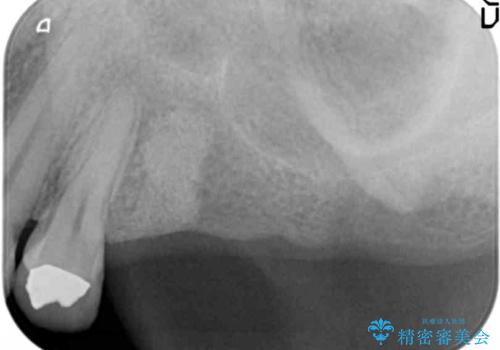

- 奥歯に入れていたブリッジがダメになり歯を抜去、全然噛めなくなった、インプラント治療を受けたい!と奥歯の機能回復を希望され来院されました。

奥歯はすでに3本失った状態で、この状態で歯を入れるには「入れ歯」か、「インプラント」の2択となります。

- 110万円(インプラント×2・チタンカスタムアバットメント×2・ジルコニアクラウン×3・仮歯×3)費用は治療当時の料金となります